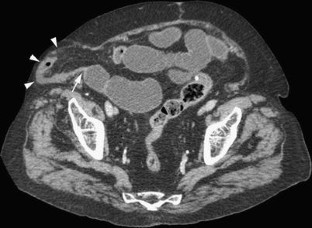

Fig. 2